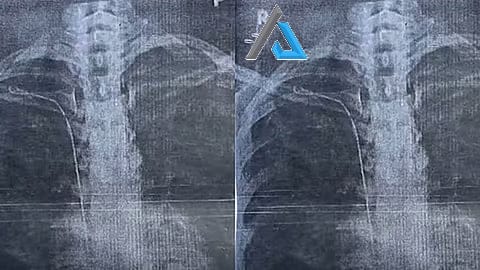

*തിരുവനന്തപുരം* : ഇരുപത്തിയാറുകാരിയുടെ ജീവിതം വഴിമുട്ടിച്ച് തിരുവനന്തപുരം ജനറൽ ആശുപത്രിയിലെ ഗുരുതര ചികിത്സ പിഴവ്. തൈറോയ്ഡ് ഗ്രന്ഥി നീക്കം ചെയ്യൽ ശസ്ത്രക്രിയയ്ക്കിടെ 50 സെന്‍റീ മീറ്റർ നീളമുള്ള സർജിക്കൽ ട്യൂബ് യുവതിയുടെ നെഞ്ചിൽ കുടുങ്ങി. കാട്ടാക്കട സ്വദേശി സുമയ്യയുടെ നെഞ്ചിലാണ് സർജറിക്കിടെ ട്യൂബ് കുടുങ്ങിയത്. ഇതുസംബന്ധിച്ച് ജനറൽ ആശുപത്രിയിലെ ഡോക്റ്റർ രാജീവ്‌ കുമാറിനെതിരേയാണ് യുവതി പരാതി നൽകിയത്. 2023 മാർച്ച്‌ 22നാണ് യുവതി സർജറിക്ക് വിധേയയായത്.

ആരോഗ്യ പ്രശ്നം ഉണ്ടായപ്പോൾ ഇതേ ഡോക്റ്റർക്ക് കീഴിൽ രണ്ടു വർഷം ചികിത്സ തുടർന്നു. ആരോഗ്യപ്രശ്നം കടുത്തപ്പോൾ മറ്റൊരു ആശുപത്രിയിൽ ചികിത്സ തേടി. എക്സ്റേയിലാണ് നെഞ്ചിനകത്ത് ട്യൂബ് കണ്ടത്. വീണ്ടും സന്ദർശിച്ചപ്പോൾ ഡോക്റ്റർ പിഴവ് സമ്മതിച്ചെന്ന് യുവതി പറഞ്ഞു. മറ്റു ഡോക്റ്റർമാരുമായി സംസാരിച്ച രാജീവ്‌ കുമാർ കീ ഹോൾ സർജറിയിലൂടെ ട്യൂബ് പുറത്തെടുക്കാമെന്ന് യുവതിയെ അറിയിക്കുകയും ചെയ്തു.

സംഭവം രഹസ്യമാക്കിവയ്ക്കണമെന്ന് ഡോക്റ്റർ ആവശ്യപ്പെട്ടതായും യുവതി വെളിപ്പെടുത്തി. പിന്നീട് രാജീവ്‌ കുമാറിന്‍റെ നിർദേശപ്രകാരം ശ്രീചിത്ര ആശുപത്രിയിൽ ചികിത്സ തേടി. രക്തക്കുഴലുമായി ട്യൂബ് ഒട്ടിച്ചേർന്നെന്ന് സിടി സ്കാനിൽ വ്യക്തമായി.